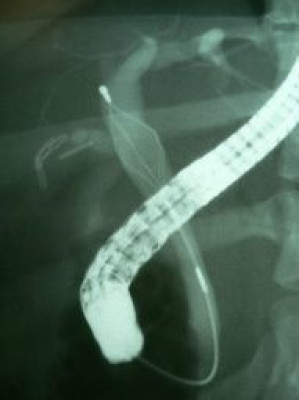

Coledocolitiasis con antecedente de colecistectomía por laparoscopía

Envíado por Dr. Carlos Miguel Zavaleta Consuegra